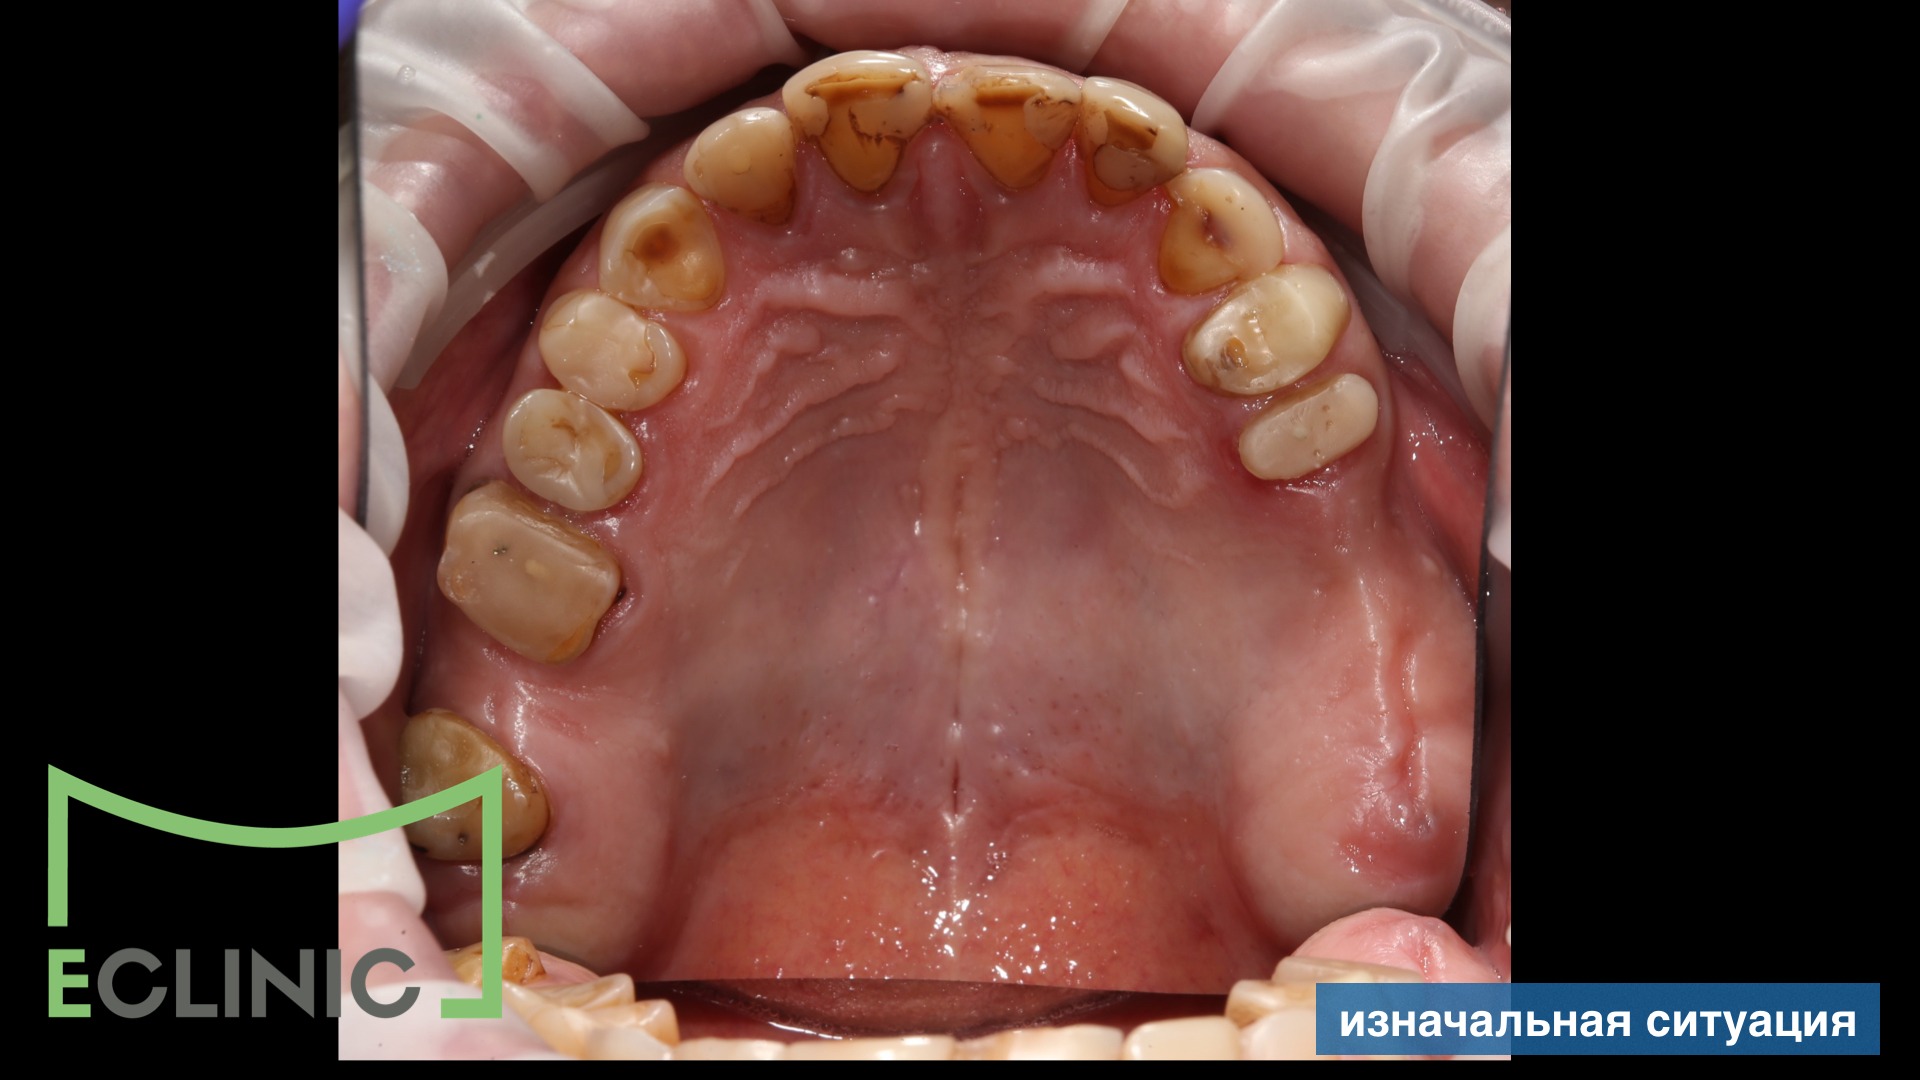

К нам в клинику обратился мужчина с желанием привести зубы в порядок

Совместно с хирургом был составлен план лечения, включающий имплантацию.

После окончания хирургического и эндодонтического этапов, для снижения мыщечного тонуса и восстановления комфортной позиции нижней челюсти была проведена сплинт терапия на миорелаксационной шине.